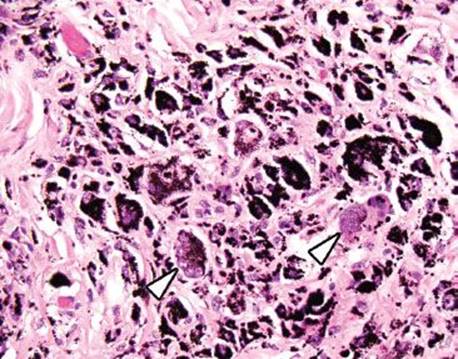

Pneumatosis cystoides intestinalis (PCI) refers to cyst-like structures impregnated with gas and lined by macrophages and foreign body giant cells. These structures are within the bowel wall and can be visualized endoscopically and radiographically (Figs. 4.256–4.262). Up to 85% of PCI cases are secondary to an iatrogenic procedure, mechanical, bacterial, metabolic, or pulmonary dysfunction.123 An association with collagen tissue disorders, AIDS, and glucorticoids has also been reported. While numerous theories of origin exist, the prevailing view is that increased intraluminal pressures force gas through damaged mucosa, and a subsequent tissue response manifests as a foreign body giant cell reaction. PCI can be seen anywhere along the tubular GIT, but most cases involve the bowel (colon = 78%, small bowel = 57%).123 Patients are usually asymptomatic. When pneumatosis is identified, it is important to assure that there is not other pathology in the resection that may have initiated the rather eye-catching pneumatosis&emdash;a classic example is scleroderma (which results in sclerosis of the muscularis propria and obstruction). CMV infection is also detected in some cases. Complications include obstruction, volvulus, intussception, ischemia, and perforation. Treatment is aimed at correcting the underlying disease or conservative medical therapy, where possible. See also, Pearls & Pitfalls, Granulomatous Pattern, this chapter.

Figure 4.261 PCI. Higher power shows that the cyst-like spaces are lined by histiocytes and foreign body giant cells.

Figure 4.262 PCI. Highest power shows the bland features of the foreign body giant cells lining the empty spaces.